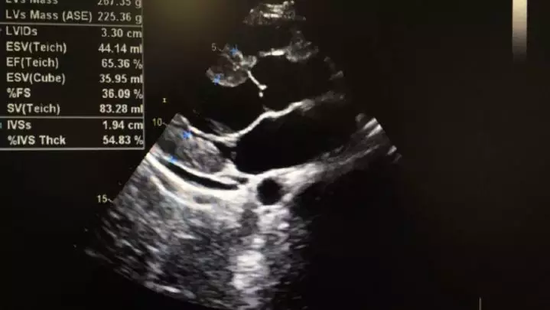

在杭州打工的父母听说儿子的事情急坏了,11月1日,小张父母将小张接到了杭州,送到浙大一院急救中心进行诊治,经过胸部CT、心电图和心脏彩超检查,发现小张的心电图ST段抬高,心肌酶谱中血清肌钙蛋白含量也高出了正常人近400倍,心肌受损情况严重;

收缩期

舒张期

在急救中心,小张进行了五天的糖皮质激素输液,并转到心内科做进一步治疗,在浙大一院经过十天的抗生素输液治疗和营养心肌的药物辅助,目前小张的心电图、心超、心脏功能等已恢复正常。